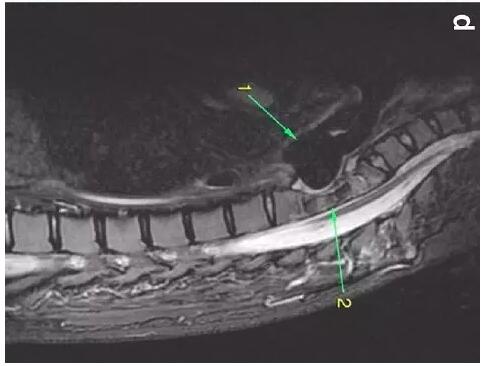

患者入住我院前行胸MRI已經(jīng)發(fā)現(xiàn)類似表現(xiàn)(圖d),當(dāng)時診斷為骨髓炎。

下圖箭頭1為氣切套管氣囊緊貼T1-4椎體水平,造成椎體前部受到侵蝕(箭頭2):

作者推測患者骨質(zhì)吸收、骨髓炎與氣切套管氣囊過度膨脹有關(guān),為氣囊過度膨脹造成椎體血流灌注降低所致。在我院住院期間,我們也發(fā)現(xiàn)高氣囊壓力才能防止漏氣。經(jīng)食道內(nèi)鏡檢查未發(fā)現(xiàn)氣管食管瘺。